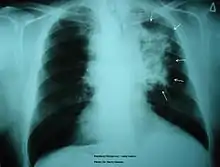

The morbidity of cigarette smoking is nearly 50% with 7 million first-hand smokers and 1.2 millions second hand smokers killed each year[8]. Regardless of active or passive smokers, macrophage accumulation is found in the lungs.[3][5] The diagnostic methods for smoke-related diseases include bronchoalveolar lavage which can also be used for examining smoker's macrophages in addition to augmented inflammatory cells in the alveolar lumen.[1]

Smoking is found to be the most important causative factor leading to COPD.[23] Because of the altered inflammatory response of the macrophages, smoking induces inflammation across the entire airway, which in turns obstructs the airflow. Symptoms of COPD include persistent coughing, wheezing, chest infections and breathlessness. Treatments for COPD usually focus on the source of the problem, which is smoking, thus the general treatment is going through smoking rehabilitation which including nicotine replacement therapy, mental therapy for advice, and support to quit smoking. In certain urgent cases, direct constriction also occurs, in which bronchodilators allow the airway to dilate.